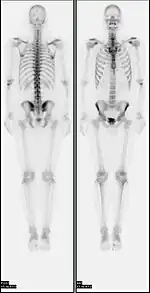

A nuclear medicine whole-body bone scan. The nuclear medicine whole-body bone scan is generally used in evaluations of various bone-related pathology, such as for bone pain, stress fracture, nonmalignant bone lesions, bone infections, or the spread of cancer to the bone.

A bone scan or bone scintigraphy /sɪnˈtɪɡrəfi/ is a nuclear medicine imaging technique of the bone. It can help diagnose a number of bone conditions, including cancer of the bone or metastasis, location of bone inflammation and fractures (that may not be visible in traditional X-ray images), and bone infection (osteomyelitis).[1]